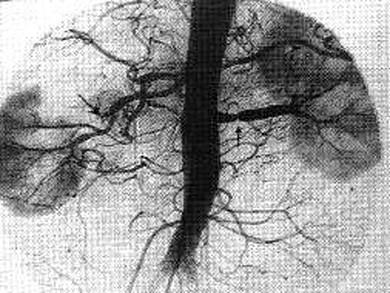

问题 女,28岁,头痛、头晕、心悸、视力减退2年,多次在当地医院检查,诊断为高血压症,用一般降压药无效,无高血压家族史。体查:血压190/110mmHg,脉搏90次/分,体型中等,心、肺、肝未见异常,腰背部闻及收缩期吹风样杂音。 关于肾血管性高血压的治疗,以下哪项不正确 ( )

选项 A、单侧肾动脉粥样硬化引起者,如对侧肾功能良好,需行肾切除 B、血管重建手术,常用的有肾动脉病变内膜剥除术等 C、自体肾移植为其治疗方法之一 D、患肾萎缩小于健肾1/2以上,肾功能严重受损,对侧肾功能良好时行肾切除术 E、经皮腔内血管成形术最适宜于血管肌纤维发育不良者

答案 A